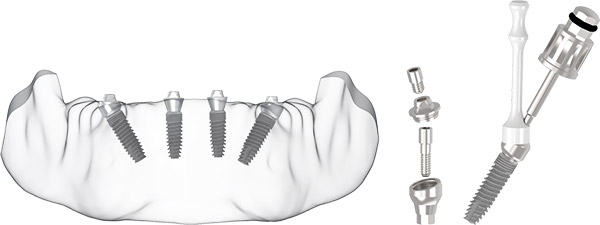

ALL-ON-FOUR

RESTORATIVE PROTOCOL

- Choose the abutment with the appropriate angle and gingival height.

- Mount the abutment by rotating the abutment until it reaches the correct position, making contact between the abutment body and the implant at the connection.

- The flexible transfer piece can be bent to facilitate abutment placement.

- For initial attachment, gently tighten the abutment screw using the driver to ensure the thread attachment.

- Remove the transfer piece from the abutment body.

Note: The recommended insertion torque for optimum abutment retention is 25 Ncm for the long screw, 15 Ncm for the short screw.